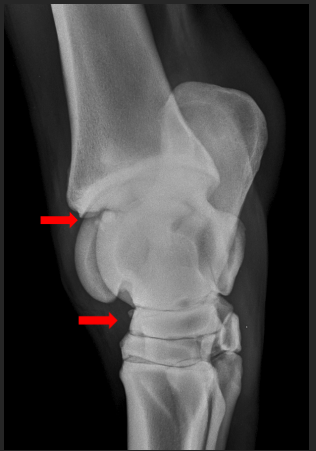

16

Q

A

incomplete ossification in a young animal